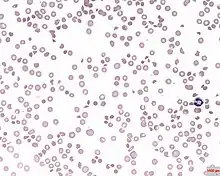

| A photomicrograph of the blood showing thrombocytopenia | |

In hematology, thrombocytopenia is a condition characterized by abnormally low levels of platelets (also known as thrombocytes) in the blood.[2] Low levels of platelets in turn may lead to prolonged or excessive bleeding. It is the most common coagulation disorder among intensive care patients and is seen in a fifth of medical patients and a third of surgical patients.[3]